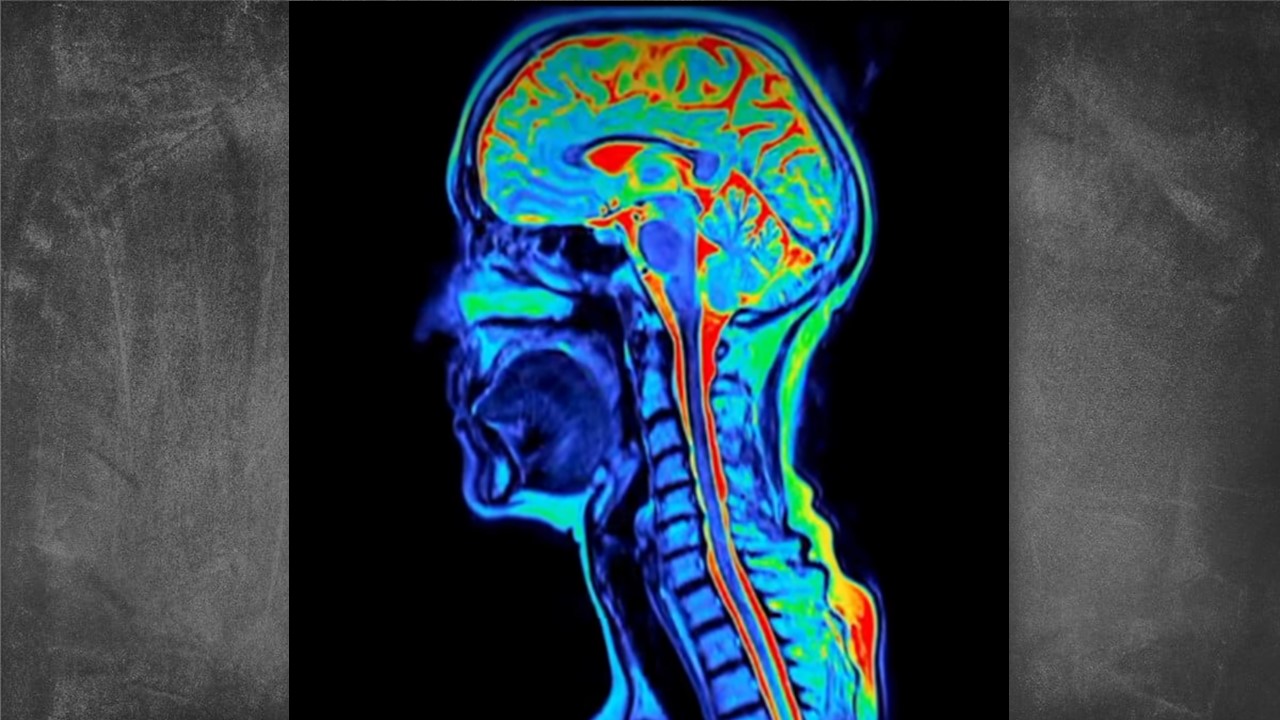

A pesquisa analisou exames cerebrais de cerca de 4 mil pessoas, com idades entre a infância e os 90 anos. O mapeamento das conexões neurais mostrou que o cérebro continua em uma espécie de “fase adolescente” até o início dos 30 anos período em que atinge seu desempenho máximo, segundo os cientistas.

As imagens revelaram que, até os 32 anos, há um fortalecimento constante das redes neurais responsáveis por raciocínio, tomada de decisão, regulação emocional e flexibilidade cognitiva. Só então o cérebro alcançaria seu “pico” de funcionamento, antes de iniciar ciclos naturais de reorganização nas décadas seguintes.